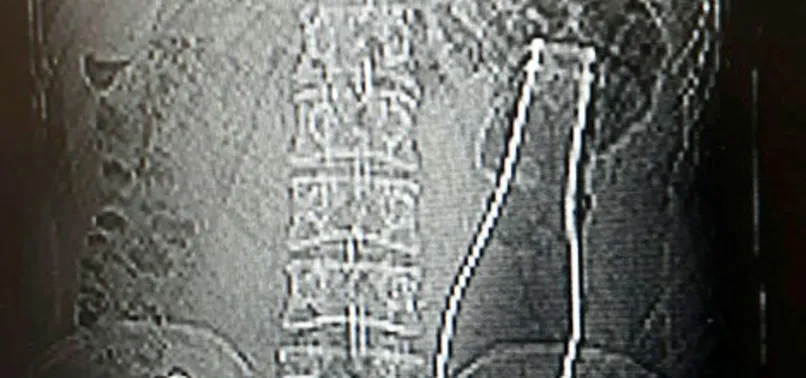

Karaman’da karın ağrısı şikayetiyle hastaneye giden 27 yaşındaki Afganistan uyruklu A.E. adlı erkeğin çekilen röntgen filminde, kalın bağırsağında şişe olduğu ortaya çıktı. Soda şişesi, yaklaşık 1 saat süren ameliyatla çıkarıldı.

Dün akşam saatlerinde Karaman Eğitim ve Araştırma Hastanesi'ne gelen A.E., doktorlara karın ağrısı şikayetinin olduğunu söyledi. Çekilen röntgen filminde A.E.'nin kalın bağırsağının bulunduğu bölgede şişe olduğu tespit edildi.

A.E.'nin makatından sokulduğu belirlenen soda şişesi, yaklaşık 1 saat süren ameliyatla çıkarıldı. A.E.'nin ifadesinde konuşmadığı öğrenilirken, polis olayla ilgili araştırma başlattı.